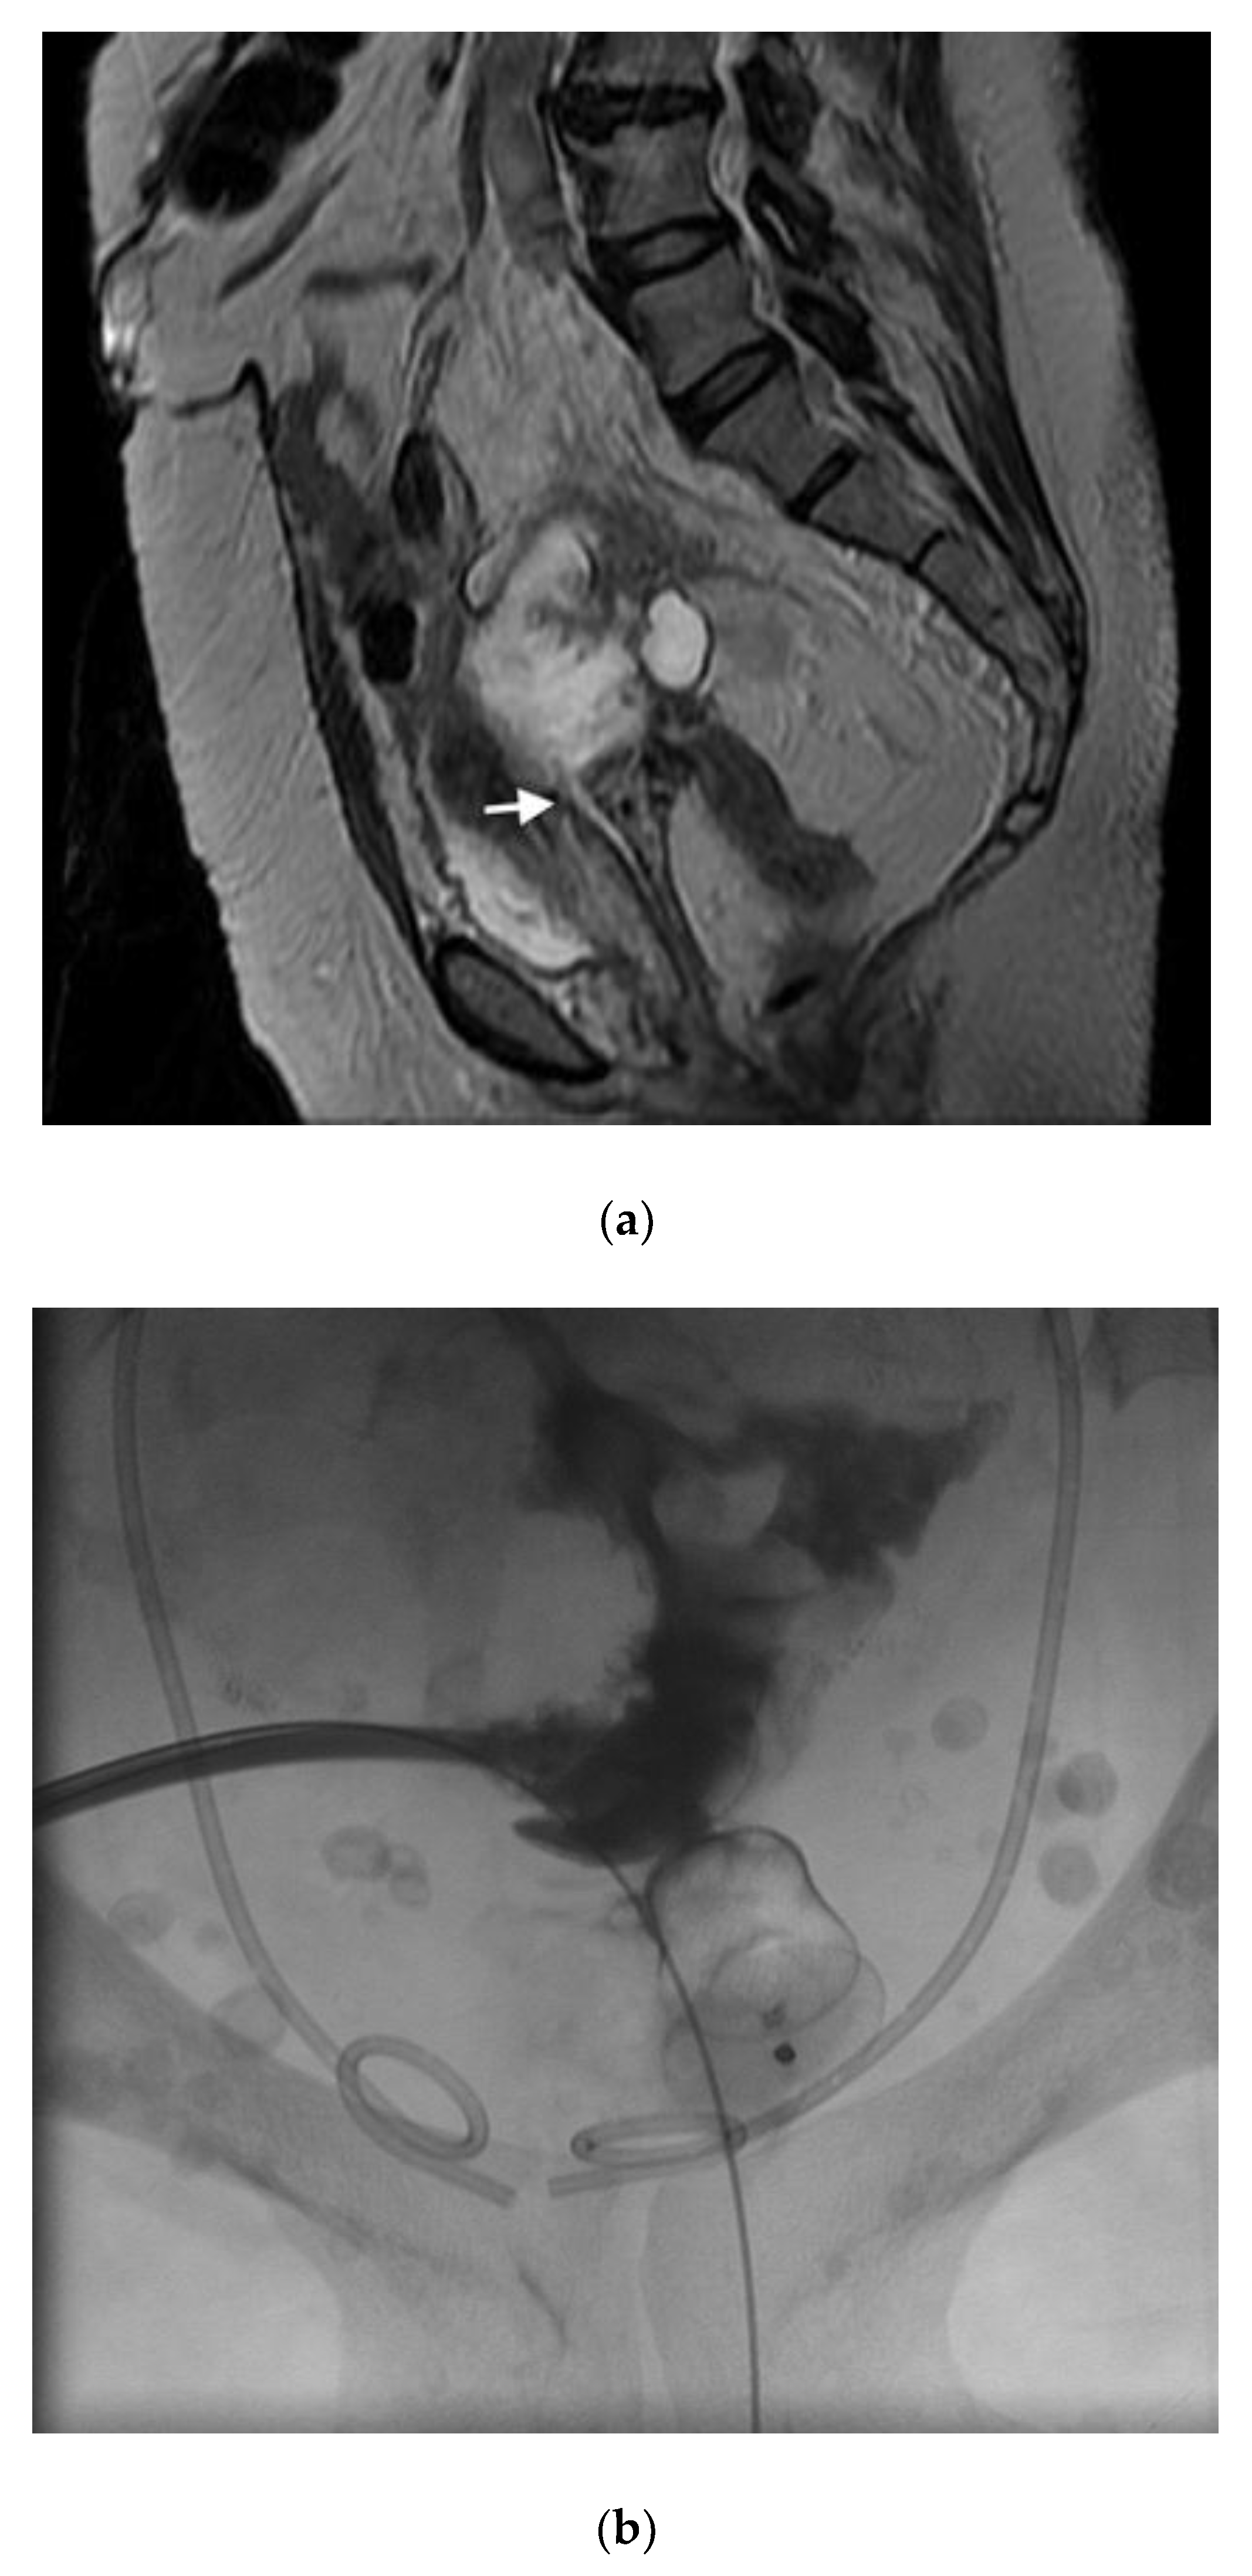

Figure 6.

(a) Sagittal T2 MR imaging shows communication between a pseudomyxomatous tumor and the vagina (arrow); (b) contrast injection shows no further communication between the tumor and the vagina just after deployment of the Amplatzer 2 plug.